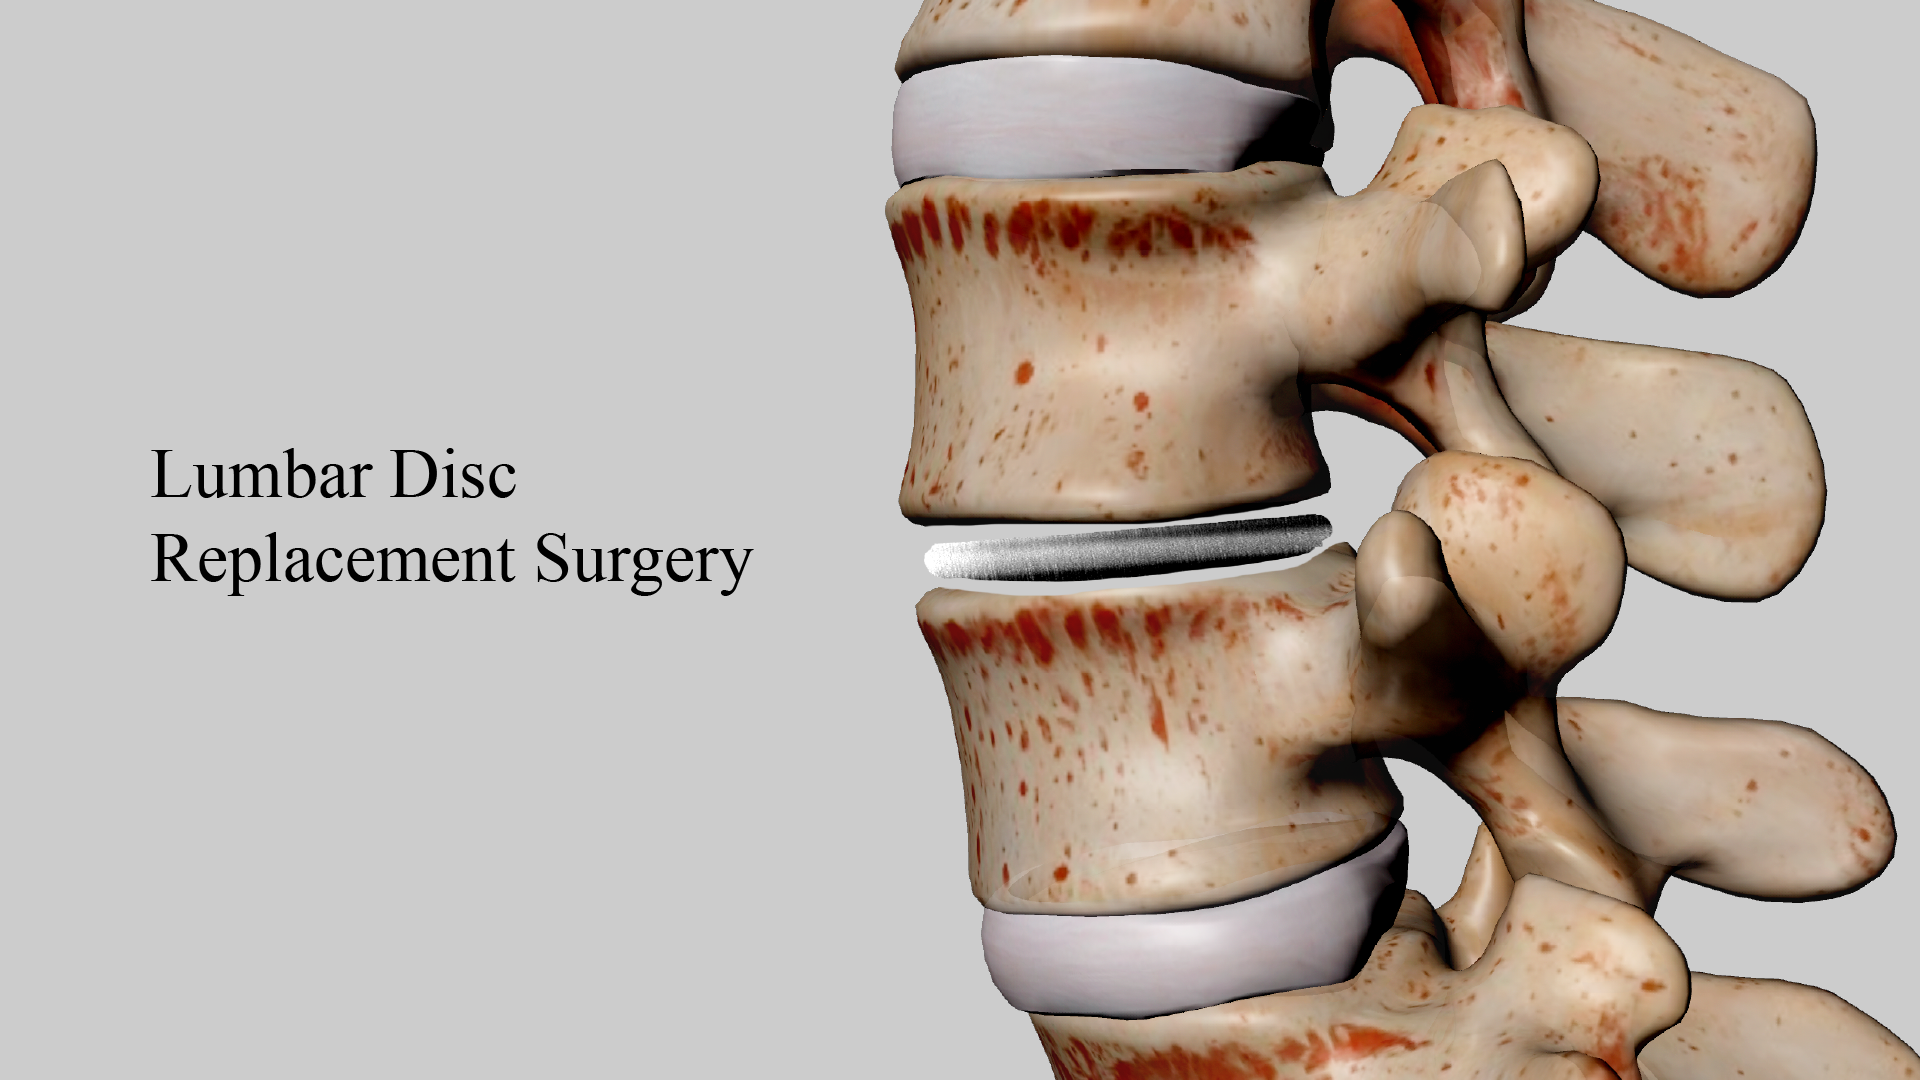

Lumbar disc replacement (LDR) is a surgical procedure designed to address degenerative or damaged lumbar discs. This technique offers a new treatment option for patients suffering from chronic back pain, providing better mobility retention and faster recovery compared to traditional spinal fusion surgery.

The fundamental principle of lumbar disc replacement surgery involves removing the damaged disc and replacing it with an artificial disc. These artificial discs are typically made from biocompatible materials such as metal and plastic, designed to mimic the function and range of motion of natural discs. This surgery aims to alleviate pain, restore normal spinal movement, and avoid potential issues associated with traditional fusion surgery.

2. Surgical Process: Under general anesthesia, the surgeon makes a small incision in the patient’s lower back, removes the damaged disc, and implants the artificial disc. The procedure typically takes 1 to 2 hours.